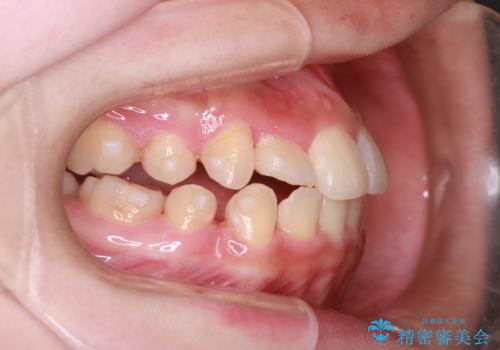

- 上下の前歯に激しい段差がある**重度の叢生(がたつき)**を主訴にご来院されました。精密検査の結果、歯をきれいに並べるためのスペースが圧倒的に不足していたため、上下左右の4番目の歯(第一小臼歯)を計4本抜歯する計画を立案しました。

ワイヤー矯正による先行治療: 最初のステージでは、ワイヤー装置を使用して抜歯したスペースへ歯を大きく移動させました。重度の叢生の場合、ワイヤーを用いることで歯のねじれや大きな移動をスピーディーに行うことができ、治療期間の短縮につながります。

インビザラインによる精密な仕上げ: 全体のがたつきが概ね整った段階で、インビザライン(マウスピース矯正)へ移行しました。透明で目立たないマウスピースを使用しながら、0.1mm単位の細かな歯の配置や、最終的な咬み合わせのバランスを精密に整えていきました。